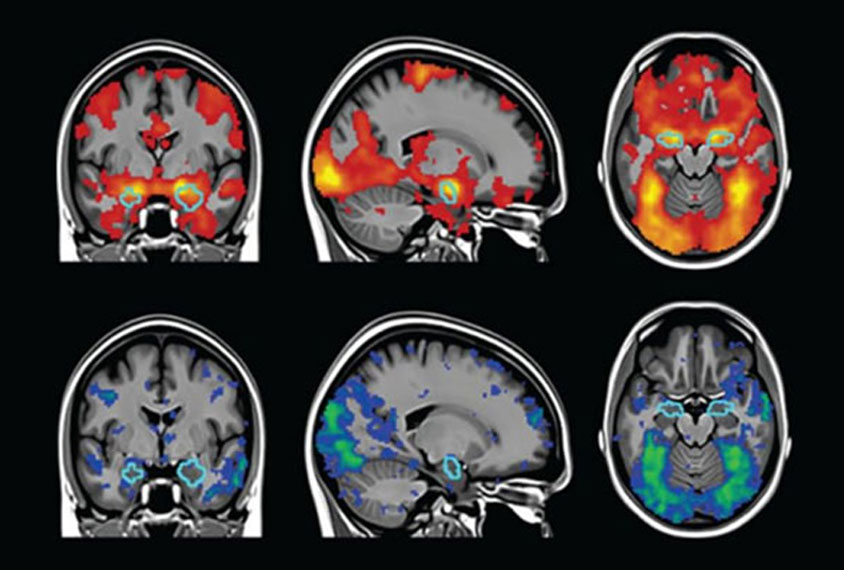

Using advanced MRI brain imaging, researchers aim to understand whether sensory enrichment—the same approach that improved outcomes in previous clinical trials—also produces measurable changes in brain structure.

Researchers will use MRI to measure whether the thickness of certain brain regions—those involved in sensation, self-regulation, and planning—changes after 24 weeks of daily enrichment activities.

If the study finds that improvements in behavior are matched by measurable brain changes, it would show that SET directly influences how the brain develops and provide key data needed to design a larger, definitive trial.